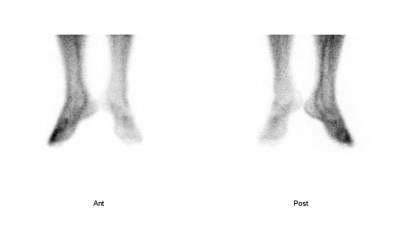

Legg-Calve-Perthes disease簡稱為LCPD,是一種自發性疾病,多發生在3-12歲的小朋友,病徵是股骨頭的血液供應突然中斷,因而導致股骨頭上的骨骺(軟骨關節面處)發生缺血性壞死,這種病的病因不明,大部分都發作於單側,這個病一開始是先由瑞典人先發現,可是因為推論病因的時候出錯,後來同時被三位學者Legg、Calve和Perthes推翻,所以才會取這麼長的名字,這種病在骨骼掃描的時候,由於患側的血流減少,因此我們可以比較兩側股骨的影像,患病的那一側在骨骺處的藥物聚積會比較少,不過因為患者多半是小朋友,加上患處的區域並不大,所以最好能使用(A)針孔式準直儀,將影像放大,這樣才容易判讀,一般來說,並不建議作SPECT,因為效果並不好。由於我們的疏忽,一直以來都很少使用針孔式準直儀來幫小朋友的股骨處造影,因此找不到可用的圖片來說明,我把一個並非罹患此病症的小朋友圖片,參考教科書的範例,以加工的方式來讓大家了解一下當罹患這種LCPD時影像上會出現什麼樣的變化,下面這張圖的左邊(病患右側)股骨是正常的,在紅圈處可以看出活度減少的情況,下次如果有這樣的病患時,我再好好的用針孔式準直儀來照相,屆時才能來更新圖片。

| 圖一:紅圈處即是患處。 |